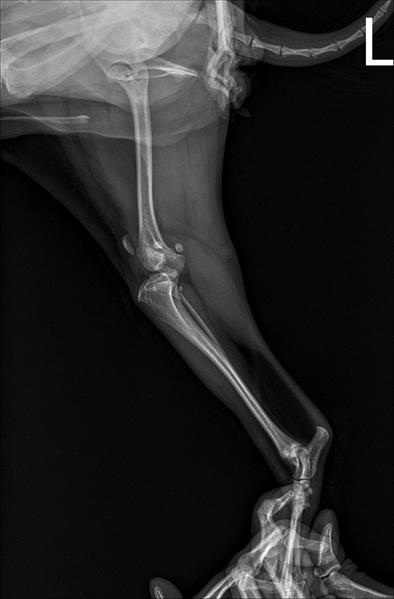

엑스레이 사진으로만 봤을 때, 슬개골 탈구 4기와 대퇴골·경골의 각변형이 보입니다.

각변형은 쉽게 말해 다리 축이 틀어진 것인데, 이 구조에서는 슬개골이 제자리에 있기가 힘듭니다.

이런 경우 슬개골만 수술한다면 잠깐 좋아질 수 있어도, 다시 탈구될 가능성이 높습니다.

각기 수술은 뼈를 정상 축으로 바로잡아 슬개골이 빠질 이유 자체를 없애는 수술이라, 우리 아이의 경우 과하지 않고 오히려 정석에 가까운 선택일 수 있습니다.